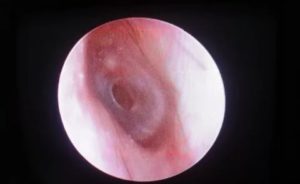

Разрыв барабанной перепонки (или перфорация тимпанальной мембраны) — это отверстие или разрыв в тонкой ткани, которая отделяет слуховой проход от среднего уха.

Наличие разрыва барабанной перепонки лор-врач может определить при визуальном осмотре с помощью осветительного прибора (отоскопа, микроскопа или эндоскопа). Врач может проводить дополнительные тесты для определения причины разрыва или степени повреждения. Эти тесты включают в себя: